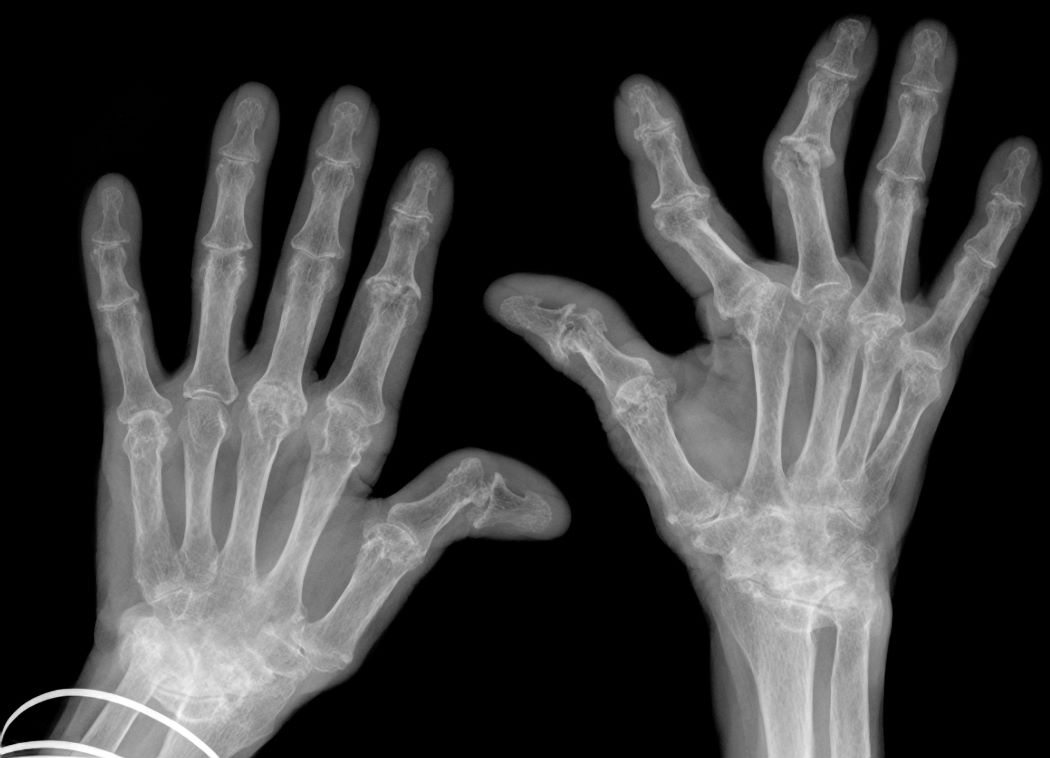

Xray of hands deformed by rheumatoid arthritis.

Speaker Dr. Cheryl Barnabe described how an outmoded treatment for rheumatoid arthritis failed to prevent this kind of deformity in an Indigenous patient's hands.

When Métis rheumatologist Dr. Cheryl Barnabe started seeing rheumatoid arthritis (RA) patients in Calgary about 16 years ago, she almost never saw hands deformed by joint inflammation.

Then one day, a First Nations woman came in whose hands were badly deformed. Barnabe learned that the system would only pay for this patient to be transported from her community to a particular town – not into Calgary – for treatment.

In this town, the woman had been receiving an outmoded injection treatment that had been standard in the 1980s, instead of a modern biologic medication.